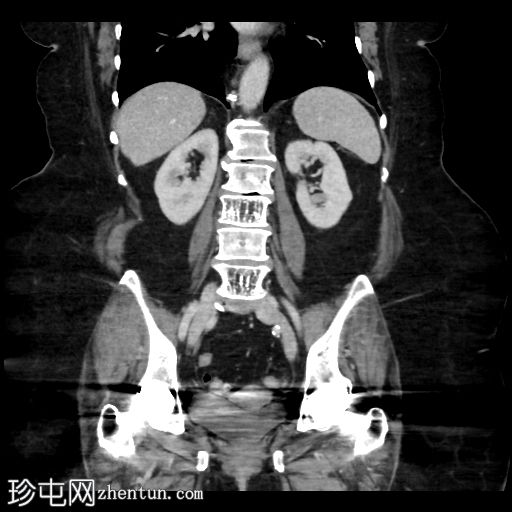

冠状位增强扫描(门静脉期)

可见小食管裂孔疝。胆道积气。胆囊增厚,相对减压,并伴有胆囊十二指肠瘘。空肠至回肠近端中度扩张,回肠近端可见节段性增厚,并延伸至右下腹的移行点。移行点处可见一枚卵圆形层状胆结石,周围有少量吞咽物。双侧全髋关节置换术导致盆腔出现条状伪影。未见其他急性异常。

这是一个典型的胆石性肠梗阻病例,伴有胆囊十二指肠瘘,移行点位于右下腹近端回肠(里格勒三联征)。请注意,肠壁在移行点附近轻度增厚,阻塞性胆结石可能与吞咽物混杂在一起,容易被忽略。此外,还应注意胆囊肠瘘可能被误认为是正常的上消化道解剖结构或十二指肠憩室。这些观察结果有助于强调全面检查的重要性。